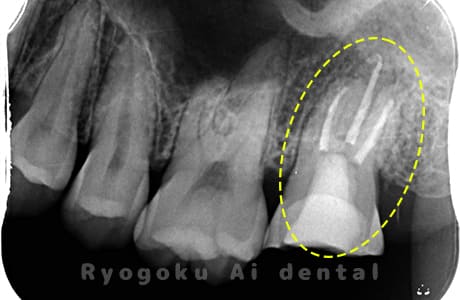

Case02

- 原因

- 慢性根尖性歯周炎

- 治療期間

- 3ヶ月

- 治療内容

- マイクロエンド

- 治療費用

- 121,000円

噛むと痛みが出る、とのことで来院した患者様です。他院での根管治療を終えてましたが、根尖病変を認めるため、マイクロエンドを行いました。